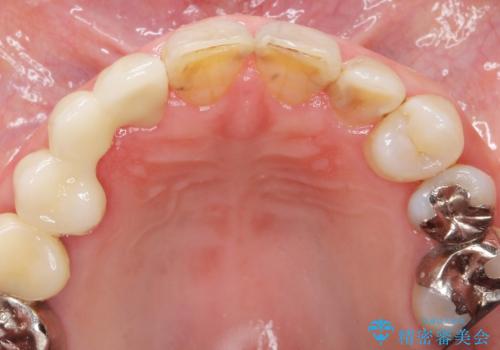

口腔内を精査したところ、右上のブリッジの内側(口蓋側)がかけており、下の前歯(右下1)には唇舌側に瘻孔を伴う大きな根尖病変ができていました。

右上のブリッジ(右上④3②)のやりかえと、下の前歯(右下1)の根管治療を行った後セラミッククラウンによる補綴治療を行いました。